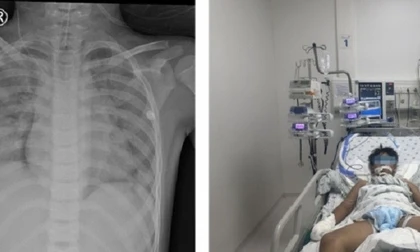

TPO - Bệnh viện Phụ sản – Nhi Đà Nẵng vừa tiếp nhận 2 trường hợp trẻ nhỏ hóc dị vật đường thở, đều liên quan đến các loại hạt thường gặp trong dịp Tết.